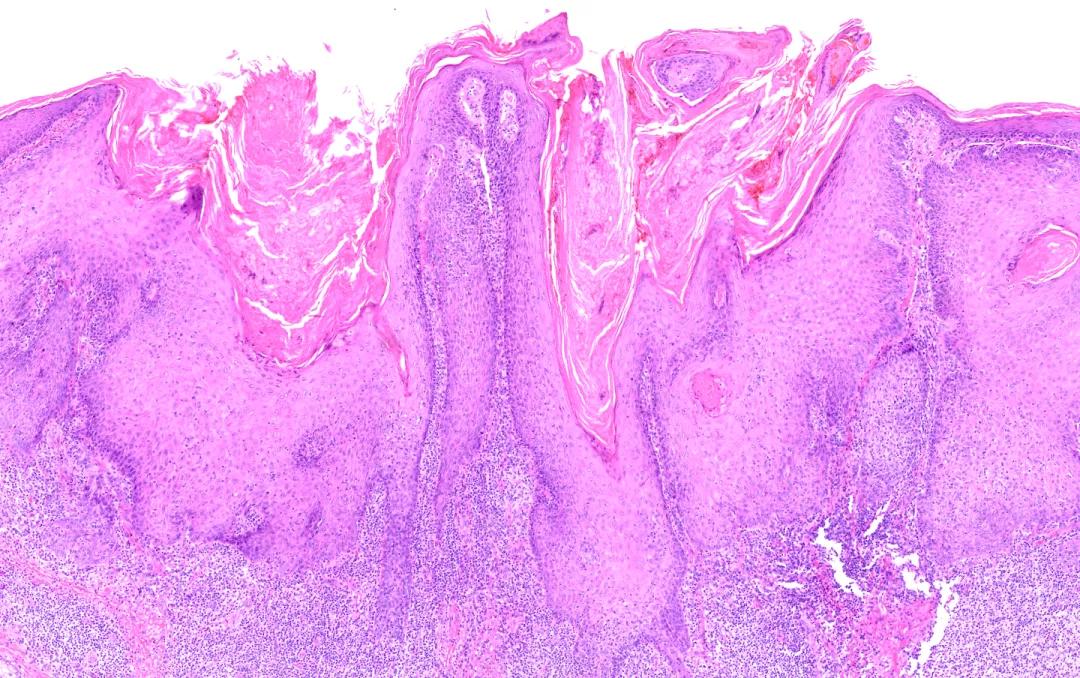

爆发的火山

这是一位角化棘皮瘤的患者,病理照片中,皮肤的角栓就像爆发的火山岩浆,皮肤的角质本是安静的存在,当它们喷涌而出,皮肤疾病也汹涌而来。